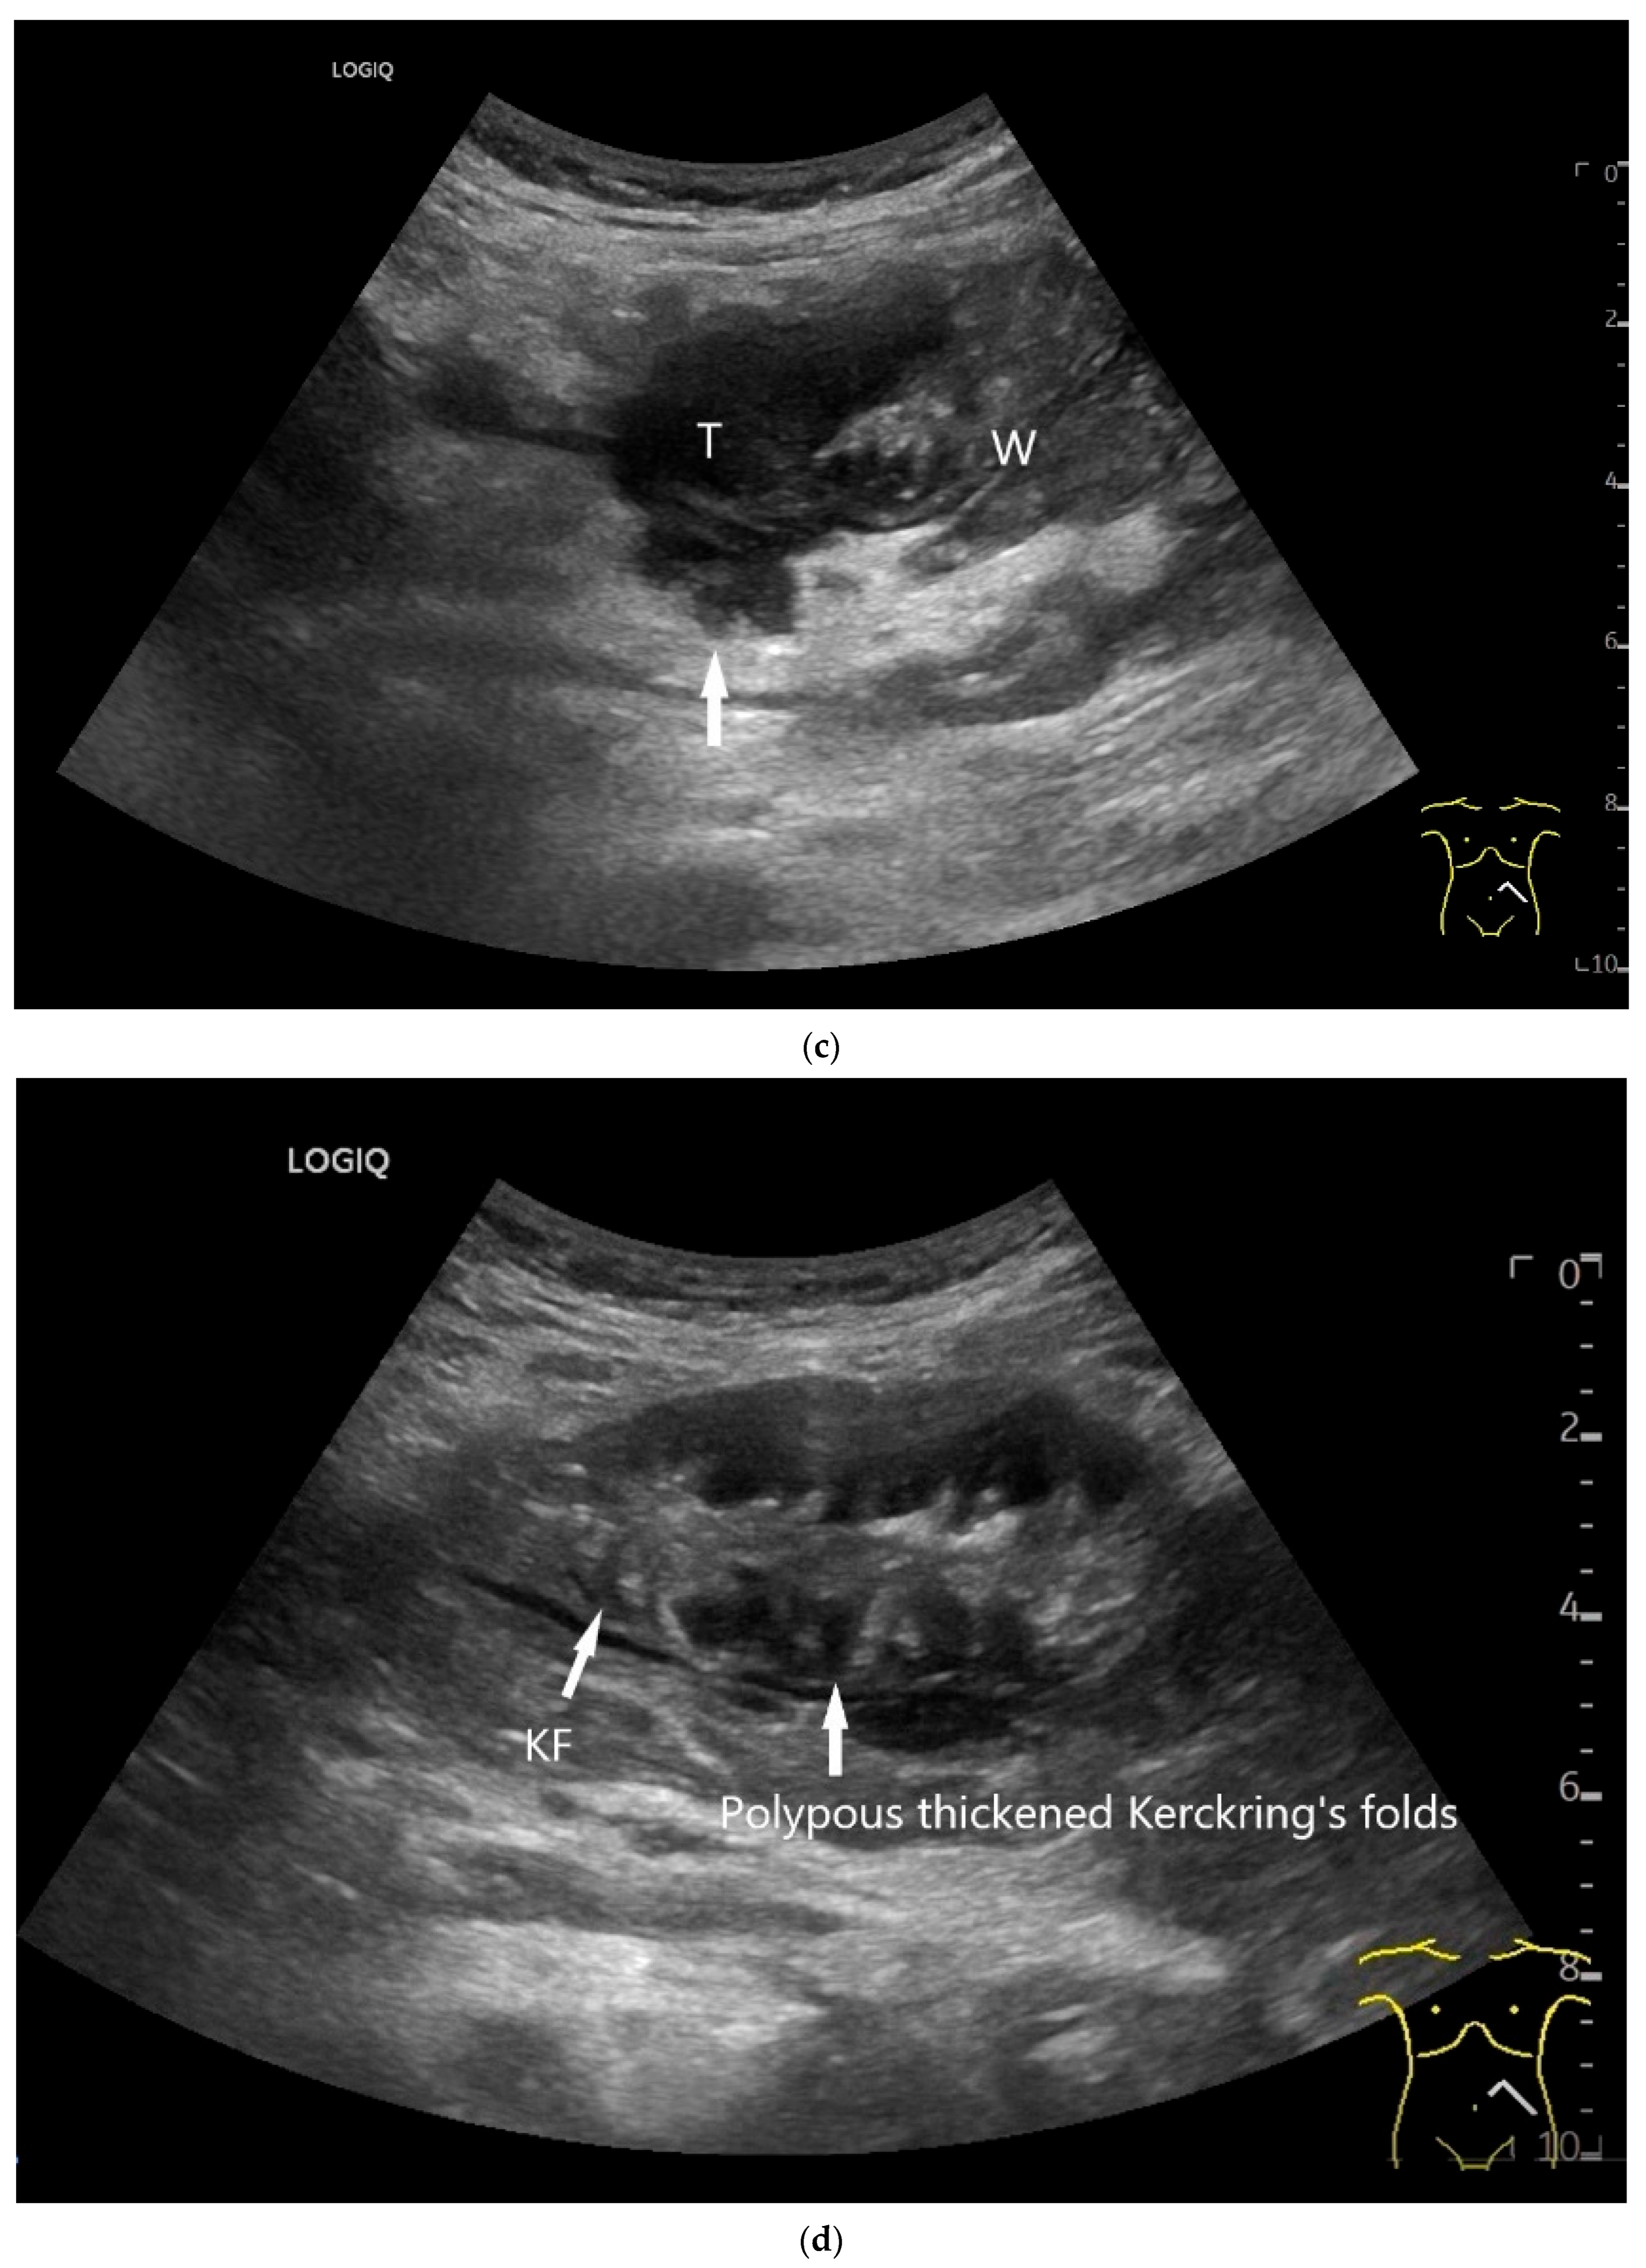

Figure 18.

Small intestine metastasis of a malignant melanoma (between the markers). Significant hypoechoic wall thickening (W) with narrowed lumen reflex (L) and lumen obstruction.

Figure 19.

Small intestine metastasis of pleural mesothelioma. Hypoechoic tumorous wall thickening (T) between the markers. The normal wall with Kerckring’s folds (KF) is visible adjacent to it. Next to the small intestine is a round hypoechoic tumor-suspicious lymph node (L).

The typical appearance of the various small intestine tumors and indirect indications are summarized in Table 5. Differential diagnoses of tumor-related wall thickening in the small intestine include inflammatory wall changes in Crohn’s disease and duodenal wall hematoma (Figure 20, Figure 21 and Figure 22). If wall thickening does not regress in long-standing Crohn’s disease under anti-inflammatory therapy and there are no explicit clinical and paraclinical signs of inflammation, the development of a tumor on the basis of Crohn’s disease must always be considered.